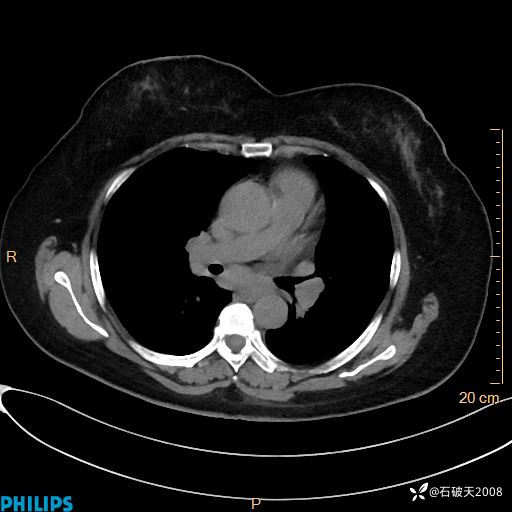

肺结节病?纵膈型肺癌?淋巴瘤?有点意思,欢迎围观

女 52岁 主 诉:咳嗽10余天,咳痰2天。

现病史:10余天前无明显诱因出现咳嗽,呈阵发性干咳,伴咽喉部发痒,无咽痛,无咳痰,无鼻塞、流涕、打喷嚏,无发热、畏寒、寒颤,无头痛、头晕,无胸闷、胸痛,无反酸、烧心,无腹痛、腹泻,无尿频、尿急,无皮疹等,在当地诊所求治,给予口服药物治疗(具体不详),病情无好转。遂在当地社区卫生服务中心开具口服药物治疗(具体不详),疗效欠佳。2天前出现咳痰,在我院门诊求治,行胸部CT提示肺部感染,建议住院,患者要求口服药物治疗,目前仍咳嗽、咳白色粘痰,白天量多,夜间自觉喉部喘鸣音,遂再次来院就诊,以“肺部感染”为诊断收入院。发病以来,神志清,精神可,饮食可,夜间睡眠差,大小便正常,近期体重无明显变化。

静脉期